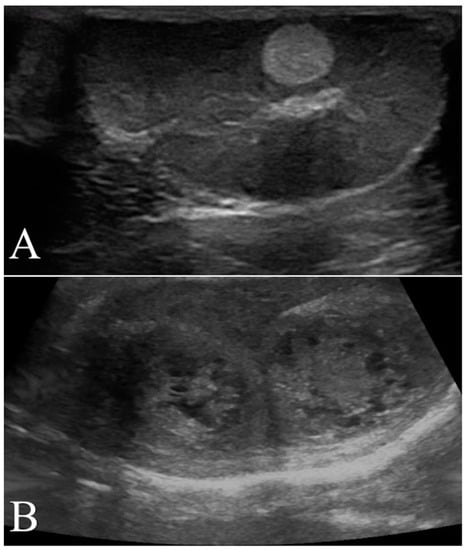

2.4. B-Flow Examination

B-flow examination was focused of the vascularization on the testicular tumor lesions. Once testicular parenchyma was visualized by B-mode, the system was switched to B-flow. Still images and video clips were saved for each location examined for subsequent analyses. The vessels of the tumor lesions were scored as 0, 1, or 2 if absent, smaller, or larger than 2 mm in diameter, respectively. Moreover, the vascularization was classified as P if the vessels were perilesional or I if distributed within the tumor lesion (Figure 3).

Figure 3. Conventional ultrasonographic scans (left panels) of two different seminomas found respectively in the right testicle of a 10 year old Labrador Retriever in (A) and in the right testicle of a 9.5 year old German shepherd in (B). In the right panel the B-flow images show the I distribution of the lesional vessels (arrow) scored as 2 in (A), while in (B) it was possible to record the P pattern of vessels distribution (arrows) scored in this case as 1. In this B-flow image, it is also possible to visualize some physiological testicular vessels (arrows head), represented by the marginal region and intra-testicular branches of testicular artery.